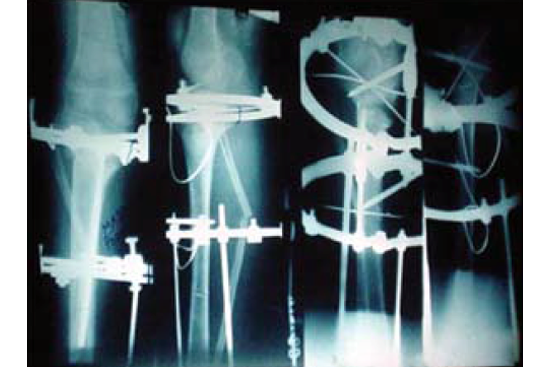

Knee Deformity